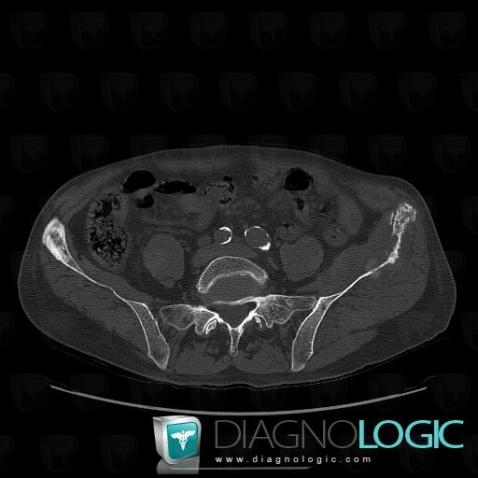

Metastasis, Ilium, CT

Here is the specific information in the key image above:

- Diagnosis Metastasis, Location(s) Ilium, with gamuts Motheaten or permeative lesion, Localised periosteal reaction, Mulltiple osteolysis